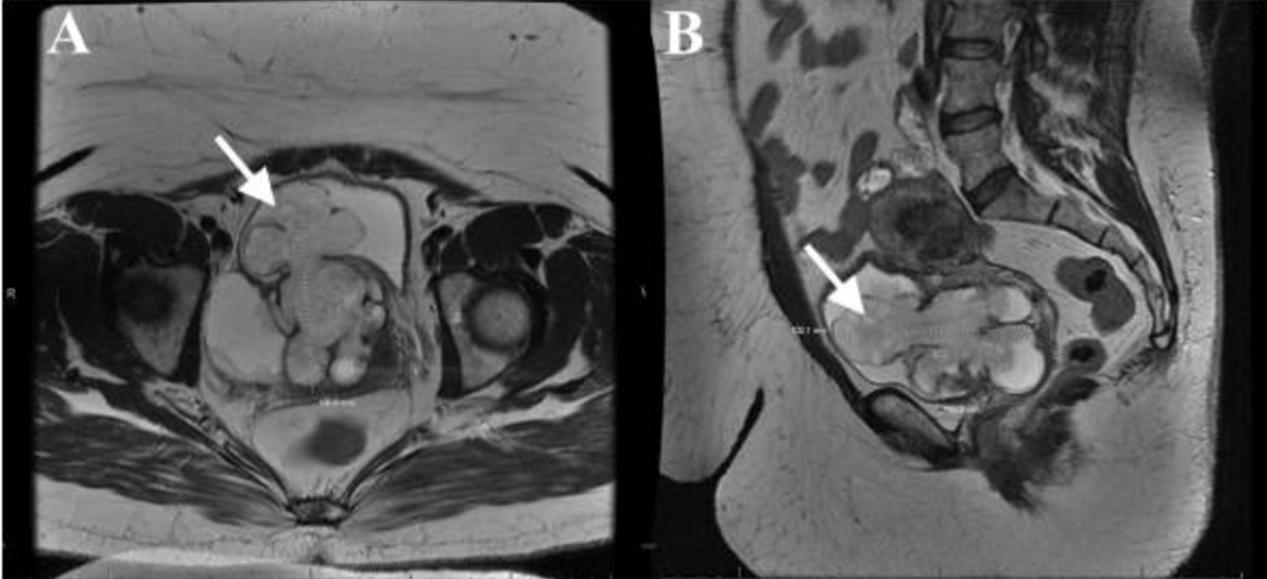

一名50岁女性,有血尿、腹痛、尿潴留和复发性尿路感染病史,超声检查发现右侧附件肿物占位。对骨盆进行了体格检查,发现右侧附件充盈。CEA、CA 19-9和CA-125指标在正常范围内。腹部及骨盆CT显示10.4×10.3×6.8cm的囊性肿物,波及膀胱、宫颈前部,可能还有右侧卵巢。膀胱镜检查显示,一个高度血管性的结节性肿物从膀胱后壁膨出,未累及输尿管口。术前MRI证实了CT检查结果(图1)

图1 (A) 横断位和(B)矢状位T2加权MRI图像显示膀胱的炎性肌纤维母细胞瘤(实心白色箭头)